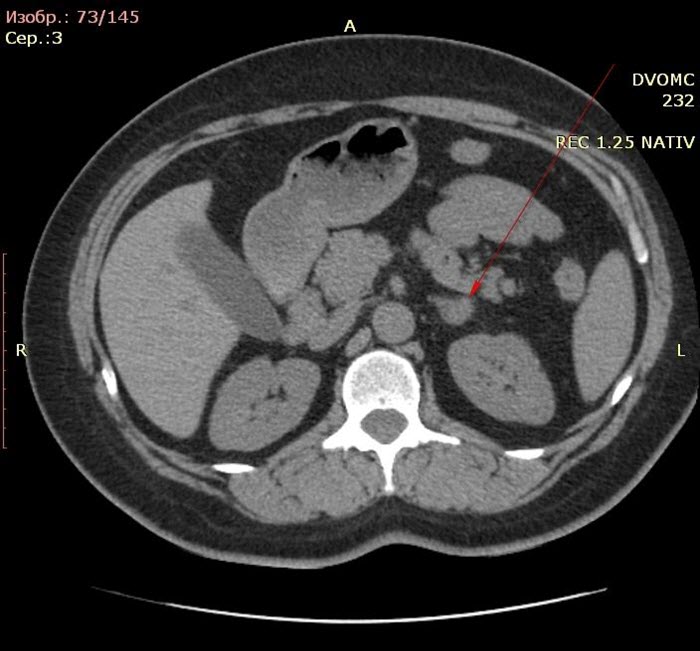

- Магнитно-резонансная или компьютерная томография гипофиза и надпочечников, а также контрастная визуализация надпочечников позволяют определить природу синдрома.

Помимо исследований, направленных на выявление причины заболевания, проводятся и другие, целью которых является оценка тяжести осложнений. Рентгенография и компьютерная томография предоставляют информацию об изменениях в костной ткани, вызванных течением болезни. Анализы крови помогают выявить такие осложнения, как диабет.